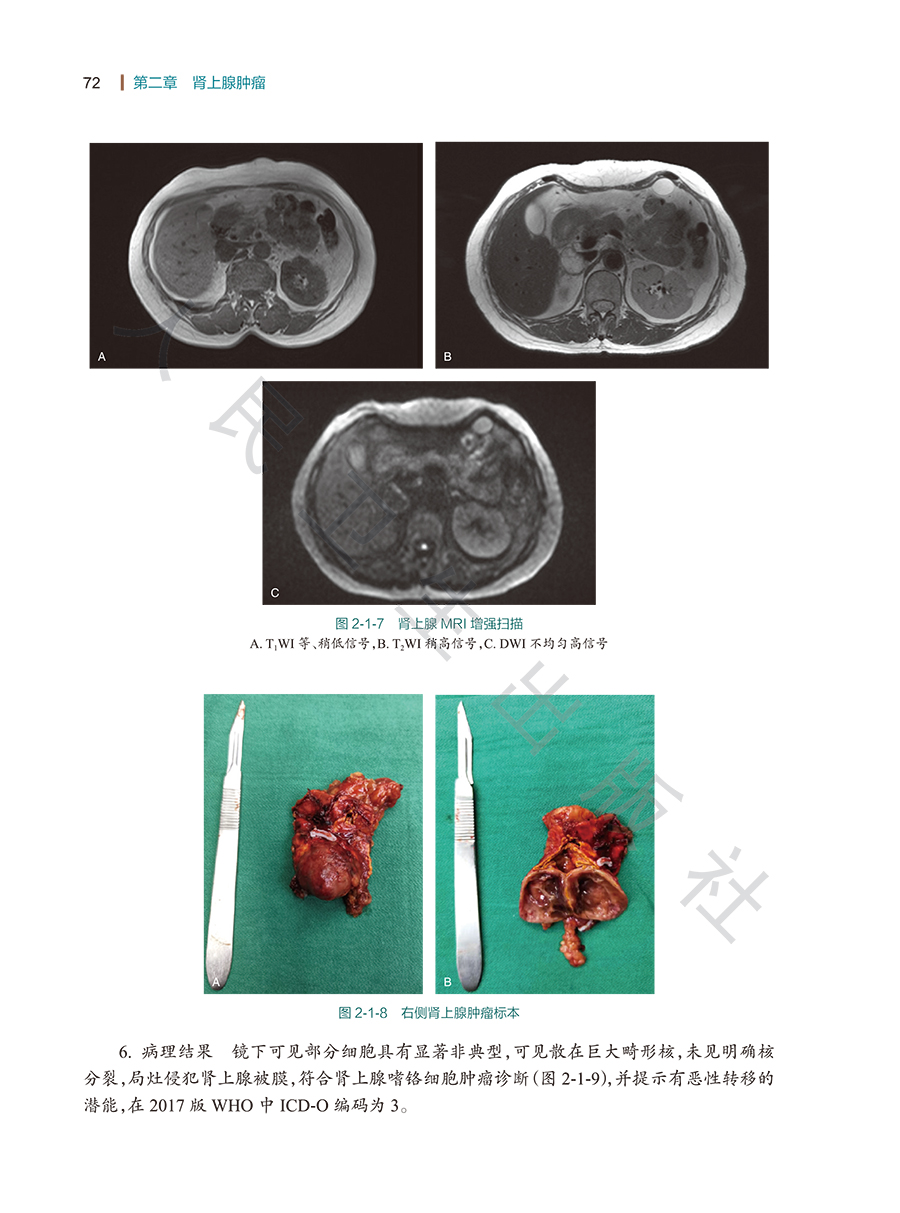

第一节嗜铬细胞瘤/67

第二节皮质醇增多症/74